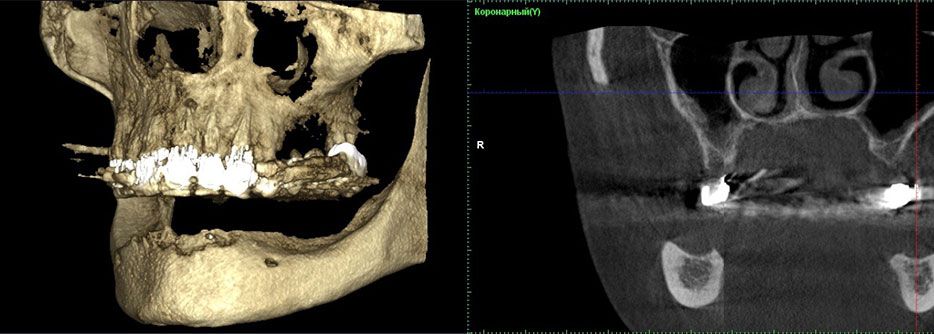

Чтобы определить возможность изготовления постоянной ортопедической конструкции, опирающейся на дентальные имплантаты, была проведена компьютерная томография (рис.1).

Рис. 1. Компьютерная томография боковой области нижней челюсти до лечения

Исследование показало, что у пациента есть костная ткань типа I согласно классификации Lekholm и Zarb.

Боковые участки, где были вставлены имплантаты, альвеолярного гребня имели ширину 10,63 мм и высоту 12,60 мм. Расстояние между кортикальной пластинкой и нижнечелюстным каналом составило всего 4,84 мм.